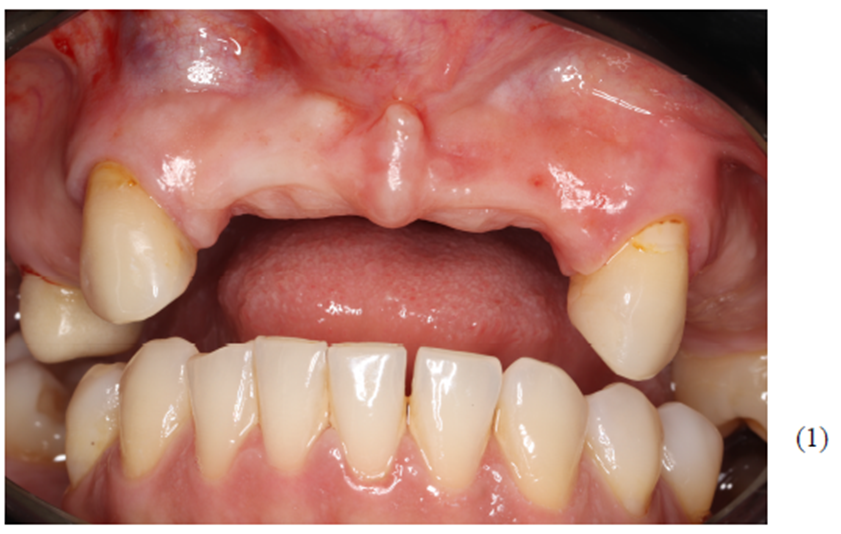

Figuras 1 e 2 – Visão intrabucal da paciente evidenciando, apesar de grande perda óssea, ótima qualidade do tecido periodontal.